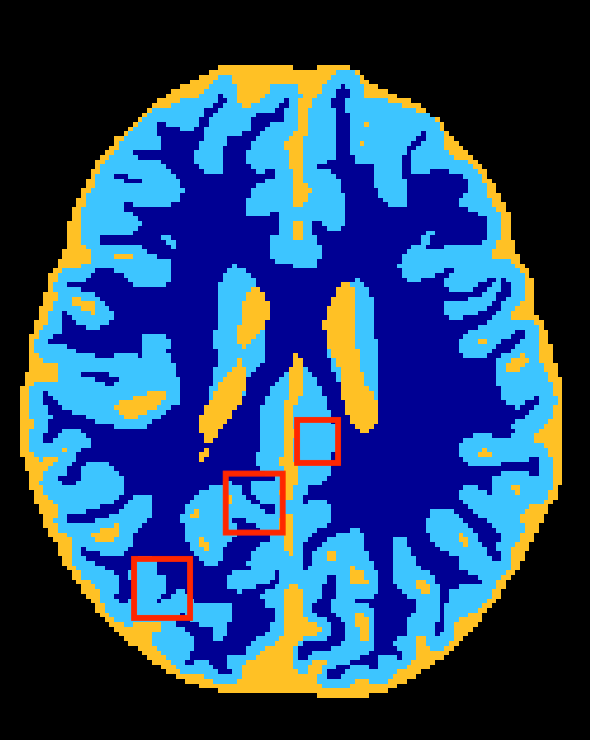

Figure 3 depicts visual results for the subject used in validation. It can be observed that HyperDenseNet (middle) recovers thin regions better than the baseline (left), which can explain improvements in distance-based metrics. As confirmed in Table 2, this effect is most prominent in boundaries between the gray and white matter. Further, HyperDenseNet produces fewer false positives for WM than the baseline, which tends to over-estimate the segmentation in this region.

Baseline

HyperDenseNet

Reference Contour